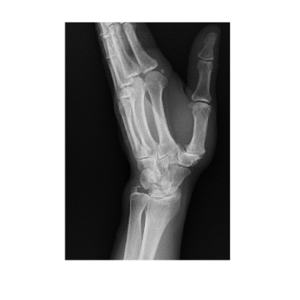

Nowoczesne zabiegi endoplastyki stawu u podstawy kciuka w naszym szpitalu.

Od listopada 2024 roku w naszym Oddziale wykonywane są zabiegi endoplastyki stawu śródręczno-nadgarstkowego pierwszego (CMC I), który znajduje się u podstawy kciuka. Jest to ważny staw odpowiedzialny za prawidłową ruchomość i sprawność ręki, szczególnie podczas czynności codziennych.

Objawy i przyczyny dolegliwości

Zmiany zwyrodnieniowe w obrębie tego stawu mogą powodować ból oraz ograniczenie ruchomości, które pacjenci najczęściej odczuwają podczas: